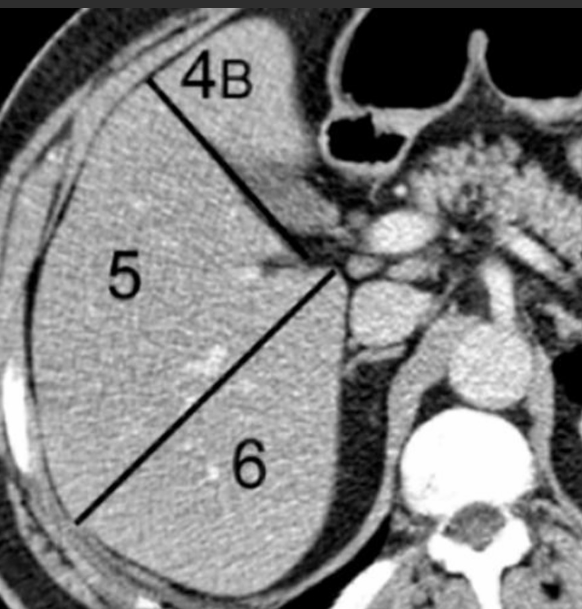

Plano divide o fígado em fígado direito e esquerdo funcionais (segmentação de Couinaud)?

A linha de Cantlie vai da fossa da vesícula biliar à veia cava inferior, seguindo a veia hepática média.

É utilizado como principal referência para a segmentação de Couinaud?

Veia porta.

A veia porta divide o fígado em segmentos supraportal e infraportal.

As veias hepáticas definem os planos verticais.

Segmentos hepáticos existem segundo Couinaud?

Oito segmentos (I a VIII).

Cada segmento é funcionalmente independente, com:

Ramo portal

Artéria hepática

Ducto biliar próprios

Vesícula biliar está em relação direta com qual (is) segmento (s) hepático (s)?

A fossa da vesícula biliar localiza-se entre os segmentos IVB e V, mais associada ao V.